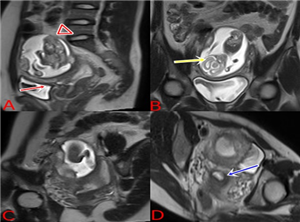

Ca lâm sàng: Thai ở sừng chột của tử cung một sừng